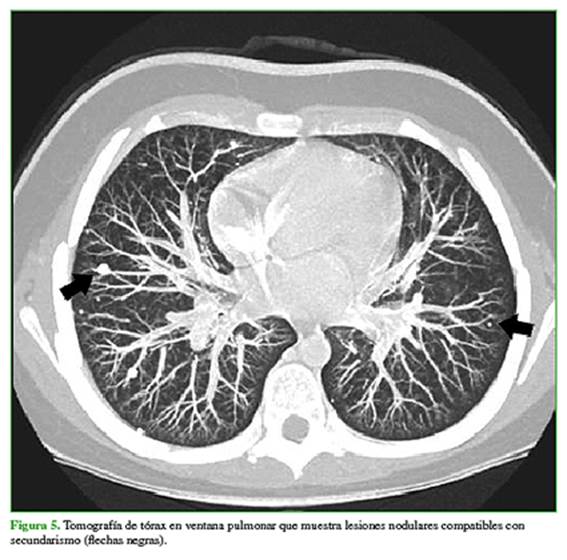

Se solicita un centellograma óseo (Figura 4) y una tomografía de tórax y abdomen para la estadificación (Figura 5).

Ante un paciente con diagnóstico de osteosarcoma proximal de tibia derecha y compromiso de partes blandas, con metástasis pulmonares bilaterales, se plantea el tratamiento con quimioterapia con 4 ciclos de metotrexato, adriamicina y cisplatino.